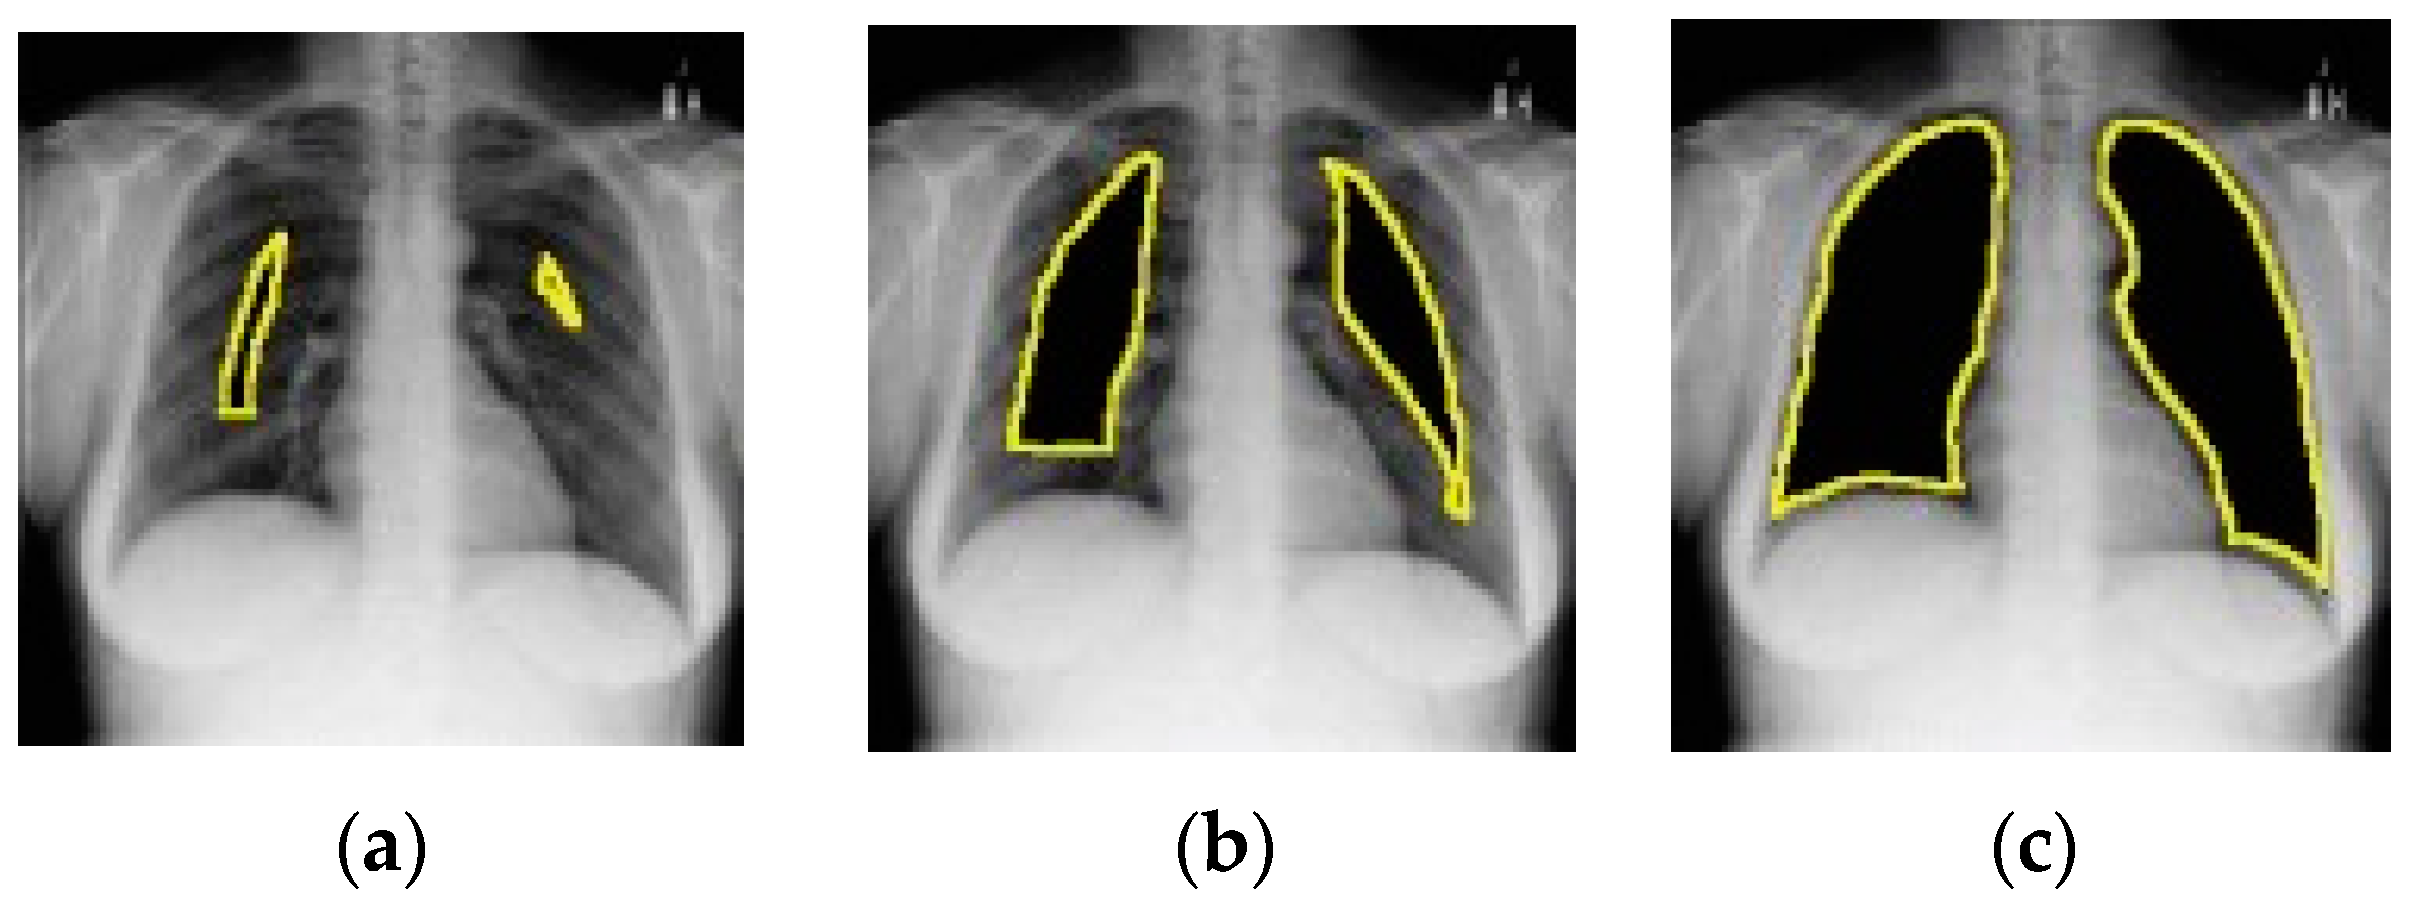

- Rahman, M.F.; Zhuang, Y.; Tseng, T.-L.B.; Pokojovy, M.; McCaffrey, P.; Walser, E.; Moen, S.; Vo, A. Improving lung region segmentation accuracy in chest X-ray images using a two-model deep learning ensemble approach. J. Vis. Commun. Image Represent. 2022, 85, 103521. [Google Scholar] [CrossRef]